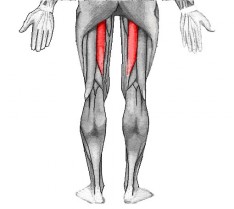

CHE COS’E’ IL SEMITENDINOSO?

Il muscolo semitendinoso è un muscolo superficiale situato nella parte postero mediale della coscia. Esso trae origine della tuberosità ischiatica e dal legamento sacrotuberoso. Il suo ventre muscolare, largo 5 cm e spesso 3, si porta verso il lato mediale tibiale dell’articolazione del ginocchio e si inserisce, mediante un sottile tendine cordoniforme, a fianco della cresta tibiale dove concorre alla costituzione della zampa d’oca, con sartorio e gracile. Insieme al semimembranoso ed al capo lungo del bicipite femorale costituisce il gruppo muscolare denominato ischiocrurali.